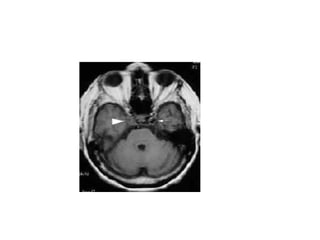

Diffusion-weighted MRI of the brain showing a large-vessel

ischemic stroke of the left middle cerebral artery (MCA) territory

Diffusion-weighted MRI ofthe brain showing a large-vessel ischemic stroke of the left middle cerebral artery (MCA) territory